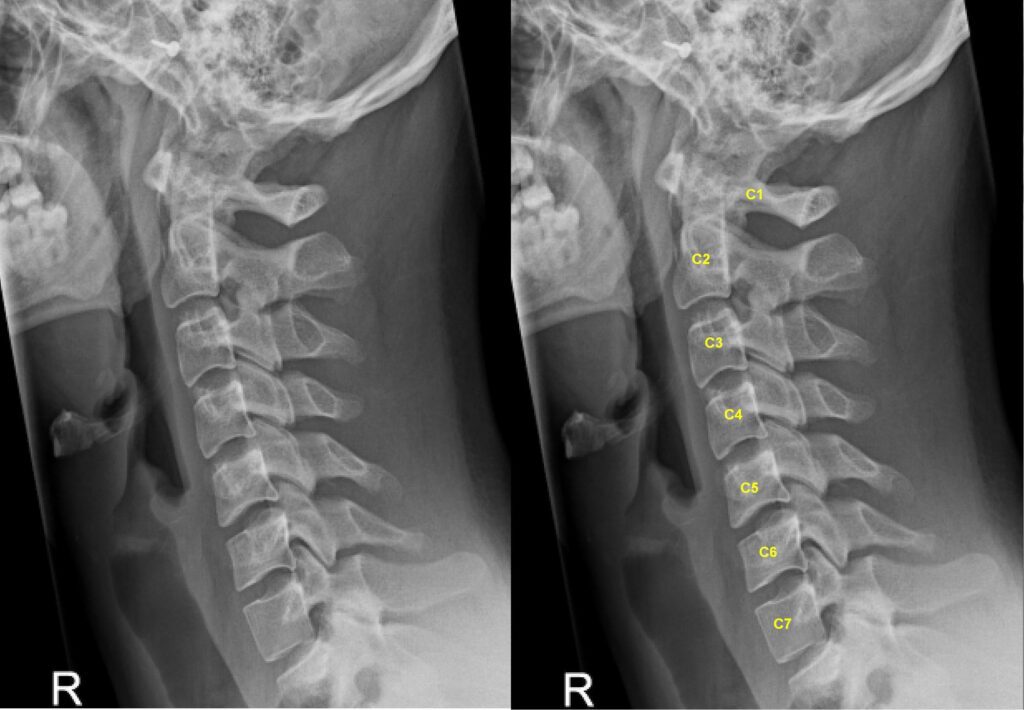

Ideally, your neck should have a slight curve. This is called cervical lordosis.

If this curve becomes straight, the head flexes double. This change creates a double chin.